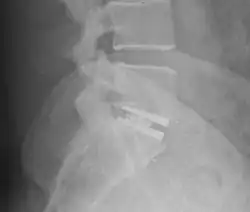

An interbody fusion cage (colloquially known as a "spine cage") is a prosthesis used in spinal fusion procedures to maintain foraminal height and decompression. They are cylindrical or square-shaped devices, and usually threaded. There are several varieties: the Harms cage, Ray cage, Pyramesh cage, InterFix cage, and lordotic LT cage, all of which are made from titanium; the Brantigan cage, made from carbon fibre; and the Cortical Bone Dowel, which is cut from allograft femur. The cages can be packed with autologous bone material in order to promote arthrodesis.[1] Such implants are inserted when the space between the spinal discs is distracted, such that the implant, when threaded, is compressed like a screw. Unthreaded implants, such as the Harms and Pyramesh cages have teeth along both surfaces that bite into the end plates.[1]

Once placed, the cages resist flexion and extension of the spine, and axial forces across the ventral and middle columns.[1]